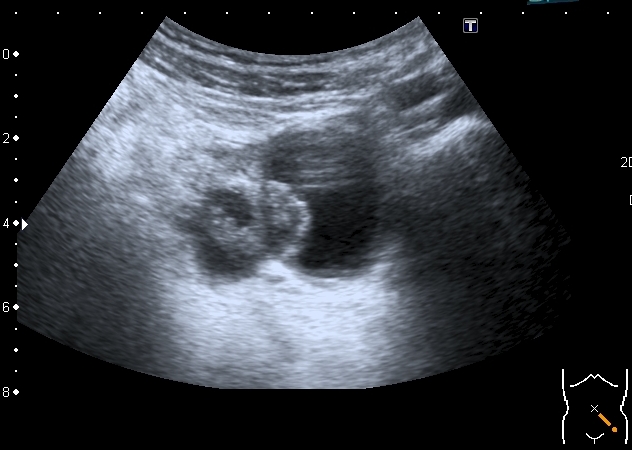

Правый яичник увеличен, с солидно - кистозными образованиями